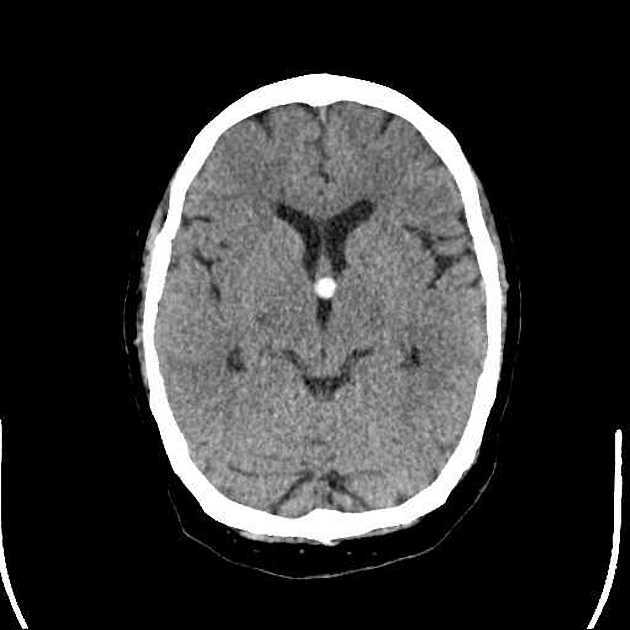

Usually the ventricular system is dilated as a result of an increased production of CSF (“overproduction hydrocephalus”).

A lobulated hyperdense soft tissue mass with a “cauliflower-like” appearance in the trigone of the left lateral ventricle with intense contrast enhancement. The ventricular system is enlarged.